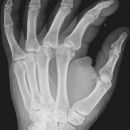

Os scaphoideum

1. Hand flach auf Kassette legen, kräftig nach lateral abduzieren. Daumen stark abspreizen.

2. Kassette mit 15° Keil unterpolstern, Daumen von Hand stark abduzieren, Handhaltung wie oben.

3. Unterarm und Hand an der radialen Seite um 45° anheben.

4. Unterarm und Hand an der ulnaren Seite um 45° anheben.

bei 1., 2. und 3.

Zentralstrahl in der Mitte der Verbindungslinie Daumensattelgelenk und Radius, sowie 1 Querfinger medialwärts.

bei 4.

In der Mitte zwischen Daumensattelgelenk und Mitte HG 2 Querfinger medialwärts.

Os scaphoideum: zwischen Daumensattelgelenk und Radius; es empfiehlt sich im Uhrzeigersinn auf der Kassette zu arbeiten.

Qualitätskriterien

Os scaphoideum soll orthograd überlagerungsfrei abgebildet sein, in den Schrägaufnahmen weitgehend überlagerungsfreie Darstellung des Os scaphoideum und der angrenzenden Handwurzelknochen. Schwer erkennbare Brüche sind oft nur in diesen Schrägaufnahmen diagnostizierbar.